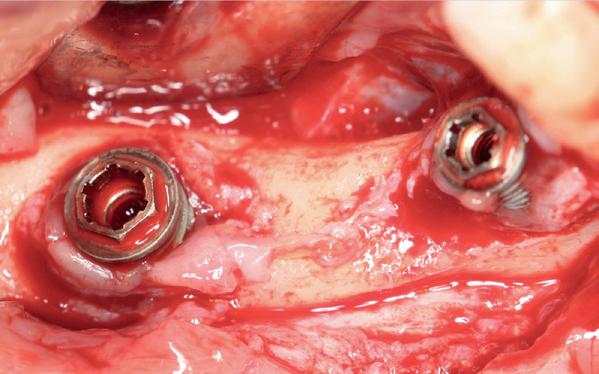

In het onderfront werd autoloog bot geoogst uit de kin regio ten behoeve van augmentatie (afbeelding

9. Botopbouw onderfront

10. OPT-implantaten

9). In de bovenkaak werd bilateraal een sinuslift uitgevoerd. Aansluitend werden in beide kaakhelften implantaten geplaatst (afbeelding 10).